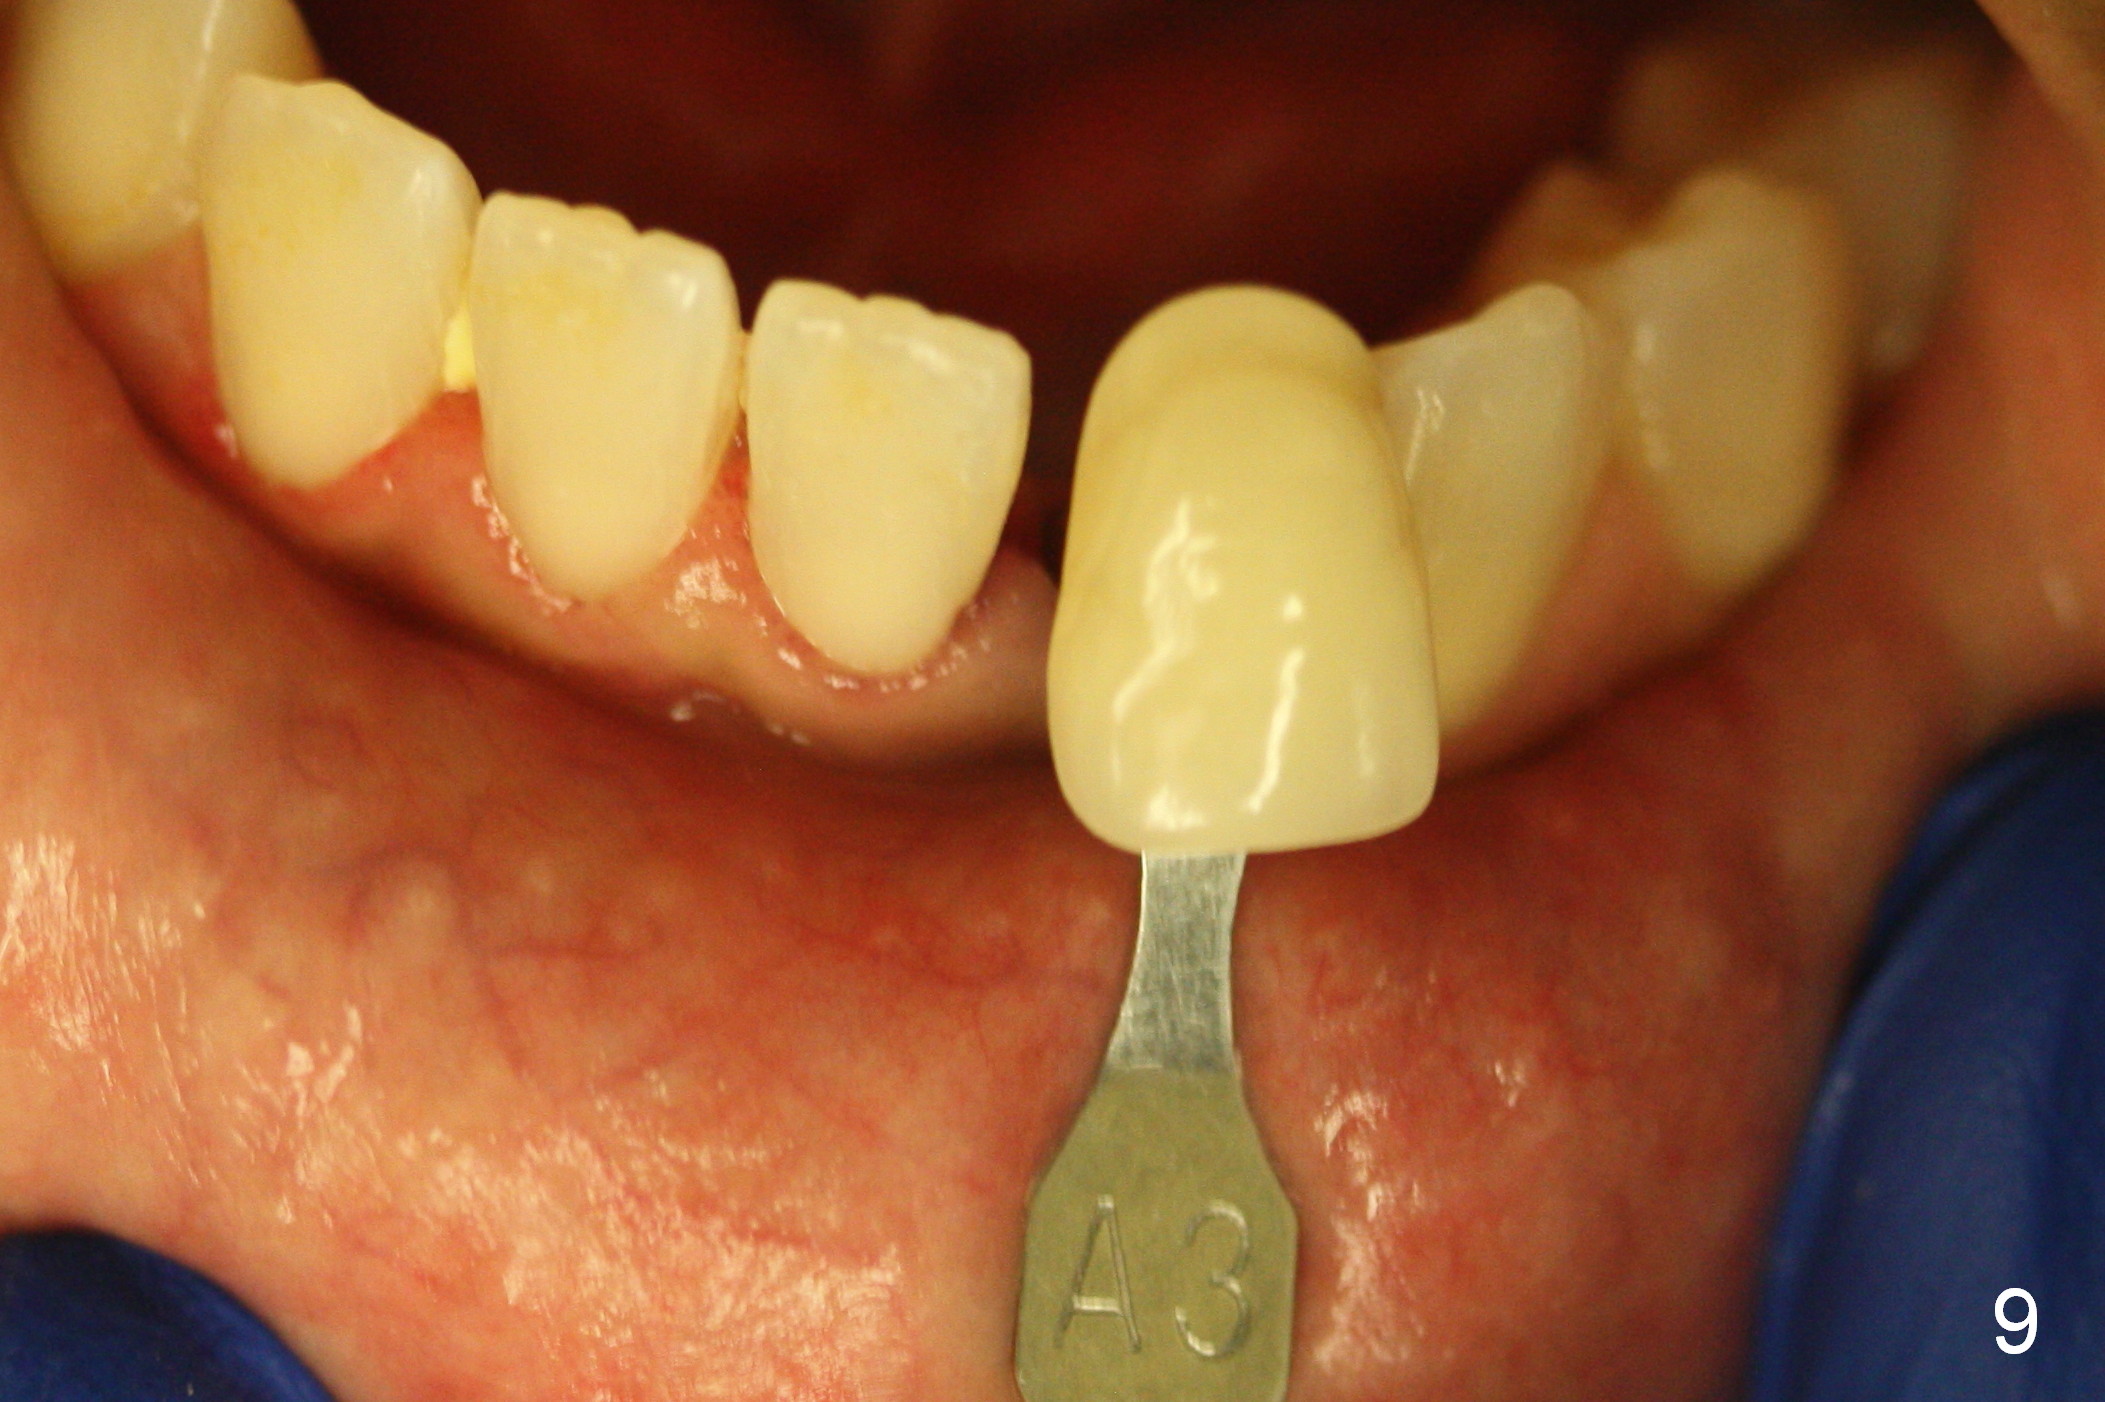

Make a new crown less transparent than the previous one (Fig.3). Can you block inside the crown to take care of the metal shade of the abutment/implant?

The original shade is A 2.5 (enclosed in the case).

Choose a shade a little darker and more yellowish (Fig.4-7 before

cleaning; Fig.9-11 after cleaning). It

appears that there is a change in shade of crown over the time.

Can you choose a Zirconia block that has the closest shade?

Do not stain or paint the crown.

Make the crown a little more bulky buccally than the

old crown (Fig.8). The implant